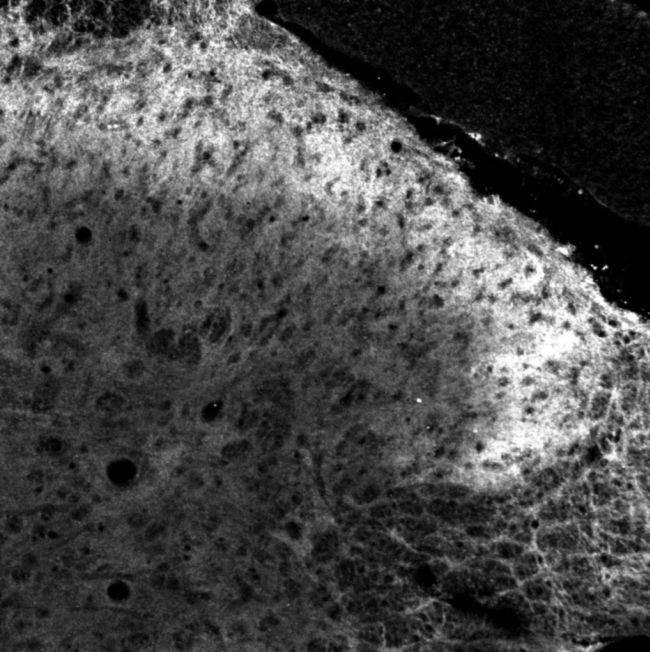

IHC-P analysis of dorsal horn of rat spinal cord using GTX79167 PACAP receptor antibody.